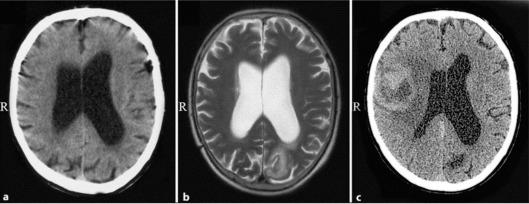

Normal pressure hydrocephalus (NPH) is a clinical and radiographic syndrome characterized by ventriculomegaly, abnormal gait, urinary incontinence, and dementia. The condition may occur due to a variety of secondary causes but may be idiopathic in approximately 50% of patients. Secondary causes may include head injury, subarachnoid hemorrhage, meningitis, and central nervous system tumor. Here, we describe two extremely rare cases of supratentorial extraventricular space-occupying processes: meningioma and glioblastoma multiforme, which initially presented with NPH.

正常压力脑积水(NPH)是一种临床和影像学综合征,其特征为脑室扩大、步态异常、尿失禁和痴呆。该病症可能由多种继发原因引起,但约50%的患者可能为特发性。继发原因可能包括头部损伤、蛛网膜下腔出血、脑膜炎和中枢神经系统肿瘤。在此,我们描述两例极其罕见的幕上脑室外占位性病变:脑膜瘤和多形性胶质母细胞瘤,它们最初表现为正常压力脑积水。